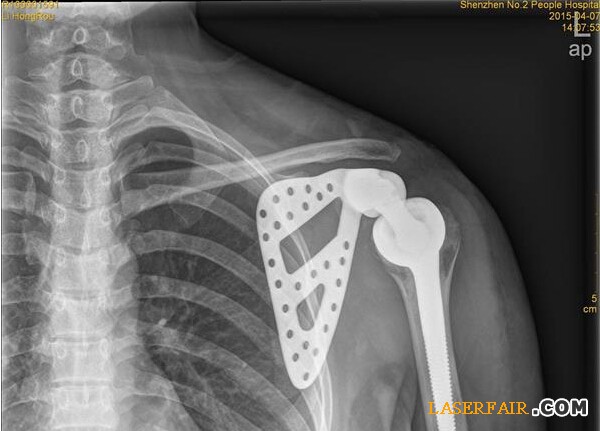

随着3D技术的日臻成熟,该医院与3D打印公司展开治疗研究,针对李女士的治疗首次采用3D打印技术制备出与患者肩胛骨完全一致的钛合金假体,并成功植入骨肿瘤患者体内。

“首先是3D打印人工制作肩胛骨模型,把采集到的李女士左边肩胛骨大小、形状等数据通过3D技术打印出完全吻合的模型。”深圳市第二人民医院骨关节、骨肿瘤科副主任医师谭纪锋介绍,然后根据模型设计出手术方案,在模型上标注手术的螺钉孔、切除边界,实现手术精准化。”由于3D模型采用的树脂材料不能直接植入人体内,因此医院将模型送至人工关节制作厂,制作出钛合金人工肩胛骨。在为李女士进行肿瘤完整切除后,再将钛合金人工肩胛骨植入患者体内。由于3D打印实现了“量体裁衣”,因而钛合金人工肩胛骨能实现精准匹配。

14日,记者从医院获悉,李女士的手术很成功,很快就可以出院了。据了解,这是深圳乃至华南地区首例肩胛骨3D打印钛合金假体植入术。